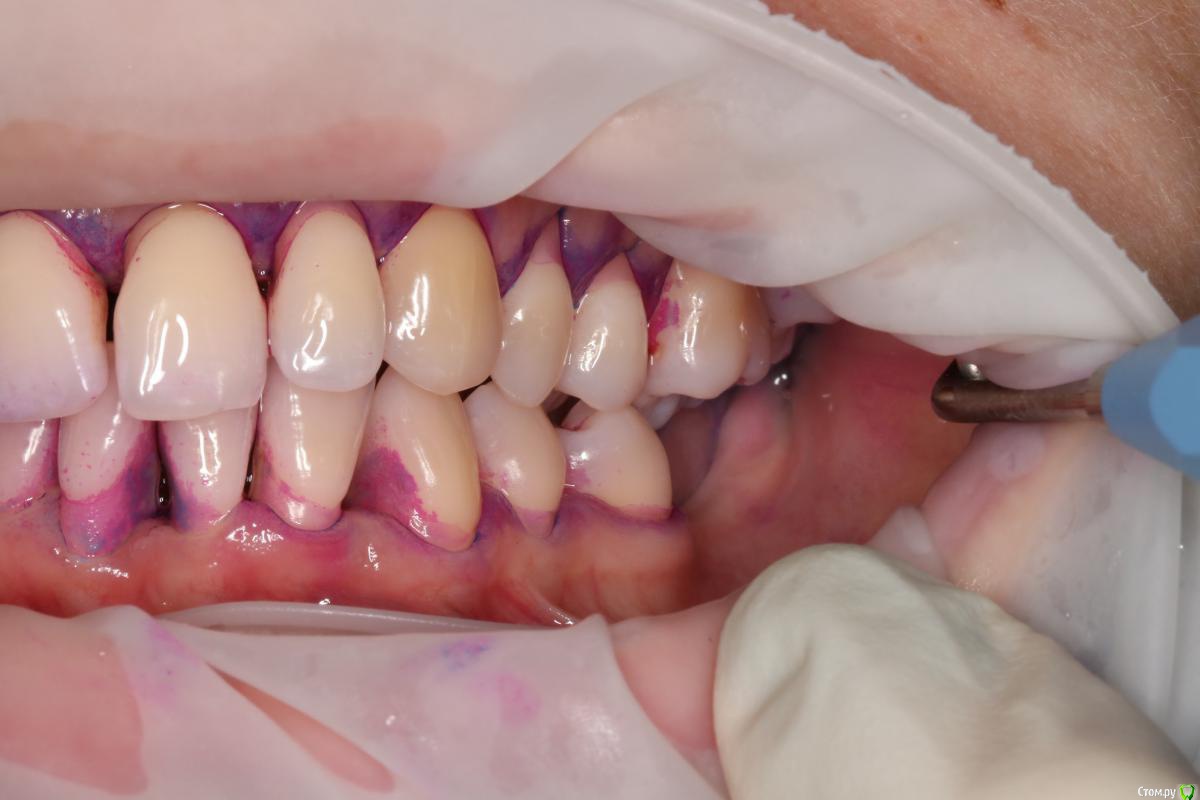

NataliaNN Опубликовано 8 ноября, 2018 Поделиться Опубликовано 8 ноября, 2018 Добрый день! У меня довольно сложная с деснами, генерализованный пародонтит, который обострился после родов и ГВ. Десны были очень воспалены, стали разворачиваться зубы. Я прошла курс чисток для лечения десен, уроки гигиены. Благодаря чему острый период воспаления прошел, сейчас состояние пародонта стабилизируется. Для дальнейшего лечения хирург планирует восстановление костной ткани на 21 и 46 зубах, и закрытие рецессий на 41, 24,25,26. А через полгода после операций можно заняться ортодонтией. Ортодонт придерживается другого мнения, сразу брекеты, а потом хирургические операции, аргументируя тем, что во время ношения брекетов результат операций может быть сведен к нулю. Хирург и ортодонт из разных клиник. Оба врача хорошие специалисты и все свои доводы аргументируют, но их точки зрения диаметрально противоположны. С чего же все-таки начать, подскажите, пожалуйста. Очень не хочется усугубить и так непростую ситуацию, к тому же все это очень затратно. Очень важно услышать мнение других специалистов. (Зубы 37,36 были потеряны в подростковом возрасте). Ссылка на комментарий

колесников Опубликовано 9 ноября, 2018 Поделиться Опубликовано 9 ноября, 2018 Не вижу смысла в ортодонтическом лечении в вашем случае (если только с 21), также сомнения в костной пластике 21,46 и в закрытии рецессии на данном этапе. Рекомендовал бы сейчас поставить импланты 36,37 с десневой пластикой , с ортопедом провести диагностику окклюзии,выявить суперконтакты,вам регулярно использовать ирригатор и через 3 мес оценить усадку десны (фронт низ-верх )и запланировать пластику рецессий. Проблема с 21 решается ортопедическим или ортодонтическим путём Ссылка на комментарий